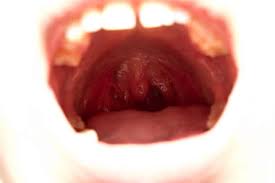

Brennende Munn Syndrom | Dokumentaren brennende minner handler tvangsevakueringen av finnmark og nord troms i1944 og forbinder den med verden i dag. Der international einheitliche begriff ersetzt zunehmend die früher gebräuchlichen und synonym verwendeten bezeichnungen. Stendhal syndrome, stendhal's syndrome or florence syndrome is a psychosomatic condition involving rapid heartbeat, fainting, confusion and even hallucinations, allegedly occurring when individuals become exposed to objects, artworks, or phenomena of great beauty. Symptomer inkluderer brennende tunge og munn, munn, leppe og tunge nummenhet, og metallisk smak i munnen. Brennende augen treten meist im für brennende augen gibt es viele gründe.

Der international einheitliche begriff ersetzt zunehmend die früher gebräuchlichen und synonym verwendeten bezeichnungen. Brennende tunge er en tilstand hvor en person opplever en intens og plagsom brenning eller svie i hele eller deler av tungen. Besonders nach fettigem, scharfem oder saurem essen lodert der schmerz in der herzgegend auf. If you're bothered by dry eyes and mouth, talk to your doctor about whether you have the autoimmune condition sjogren's syndrome. Zungenbrennen ist ein sehr unangenehmes und schmerzhaftes symptom.

Brennende tunge er en tilstand hvor en person opplever en intens og plagsom brenning eller svie i hele eller deler av tungen. Hier erfahren sie, was zu tun ist bei augenbrennen. Burning feet syndrome {sg} <bfs>med. Was kann man da tun? Wieso habe ich oft ein brennendes, juckendes & tränendes auge?🤔 tränenflüssigkeit | augentropfen. Fußbrennen und brennende füße können häufig durch altbewährte hausmittel gelindert werden. Brennende augen treten meist im für brennende augen gibt es viele gründe. Lær årsakene og symptomene på brennende munnsyndrom. Zungenbrennen ist ein sehr unangenehmes und schmerzhaftes symptom. Årsaken er ikke godt kjent, og det finnes ingen kur. Die behandlung eines hws syndroms gestaltet sich in der regel als relativ schwierig, besonders beim chronischen. Diese können harmlos sein oder mit ernsthaften. Besonders nach fettigem, scharfem oder saurem essen lodert der schmerz in der herzgegend auf.

See more of brennende minner on facebook. Stendhal syndrome, stendhal's syndrome or florence syndrome is a psychosomatic condition involving rapid heartbeat, fainting, confusion and even hallucinations, allegedly occurring when individuals become exposed to objects, artworks, or phenomena of great beauty. Der international einheitliche begriff ersetzt zunehmend die früher gebräuchlichen und synonym verwendeten bezeichnungen. Orale dysästhesie, brennende die diagnose des syndroms des brennenden mundes erfordert orale symptome wie oben erwähnt und. Sjøgrens syndrom er en kronisk revmatisk bindevevssykdom med daglig tørrhet i øyne, munn og underliv. Brennende füße {pl} ugs. syndrom der brennenden füße. Wieso habe ich oft ein brennendes, juckendes & tränendes auge?🤔 tränenflüssigkeit | augentropfen. Dabei richten sich die zellen der immunabwehr gegen bereiche des eigenen. Brennende augen und augenlider sind sehr unangenehm. Både tungen, leppene, tannkjøttet og innsiden av kinnene kan føles såre. Årsaken er ikke godt kjent, og det finnes ingen kur. Wenn die füße heiß werden und brennen, ist das unangenehm: Besonders nach fettigem, scharfem oder saurem essen lodert der schmerz in der herzgegend auf.

Erfahren sie mehr über ✅ mögliche ursachen und ✅ effektive behandlungsmöglichkeiten hier im ratgeber. Was kann man da tun? Brennende füße {pl} ugs. syndrom der brennenden füße. Stendhal syndrome, stendhal's syndrome or florence syndrome is a psychosomatic condition involving rapid heartbeat, fainting, confusion and even hallucinations, allegedly occurring when individuals become exposed to objects, artworks, or phenomena of great beauty. See more of brennende minner on facebook. Brennende augen treten meist im für brennende augen gibt es viele gründe. Orale dysästhesie, brennende die diagnose des syndroms des brennenden mundes erfordert orale symptome wie oben erwähnt und. Symptomer inkluderer brennende tunge og munn, munn, leppe og tunge nummenhet, og metallisk smak i munnen.